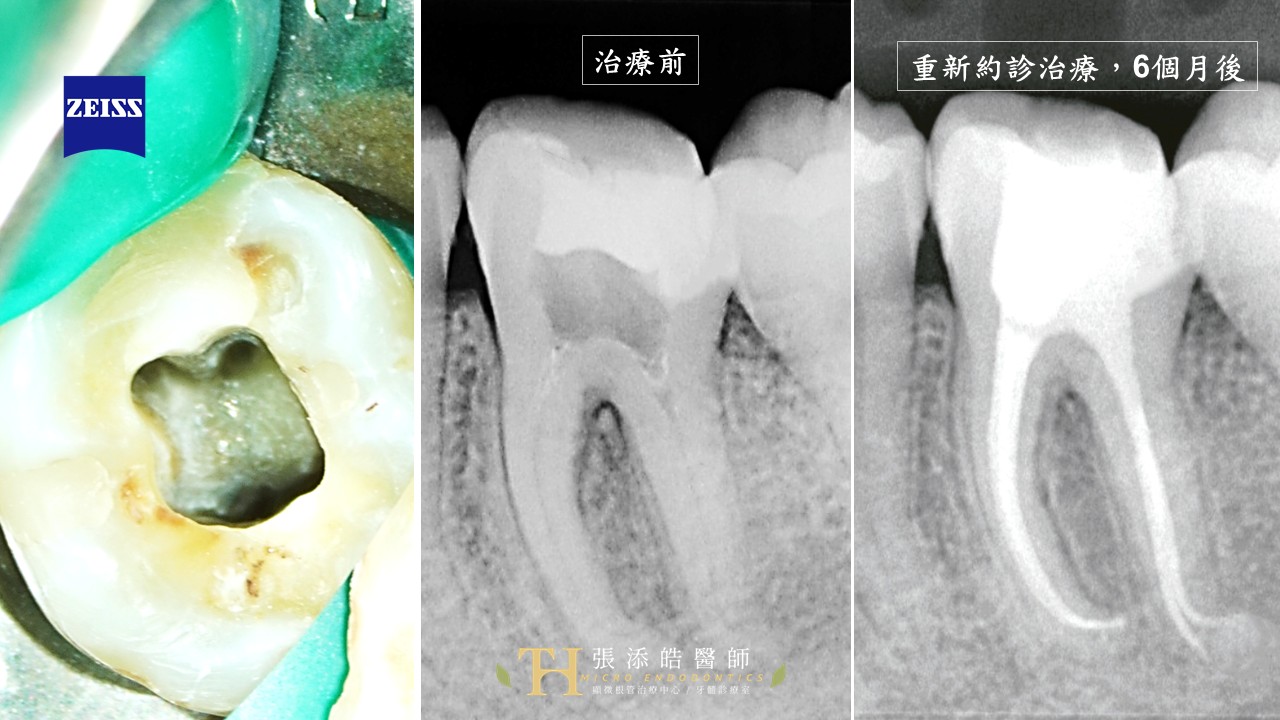

案例圖說:

這個個案,男高中生,左下大臼齒嚴重蛀牙,造成牙髓炎;需要根管治療、抽神經。

左上圖:顯微鏡下影像

在顯微鏡放大視野,可以見到根管系統的開口。

左下圖:第一次約診。

影像學上,這時候,他的牙根尖周圍骨頭,還是正常狀態,還沒有遭到侵蝕。

中圖:爽約半年後。骨頭被侵蝕掏空

影像學上,可見骨頭被侵蝕掏空,牙根尖周圍骨頭,出現黑黑的區域。

右圖:開啟重新治療,再過6個月後

影像學上,可見原本牙根尖周圍骨頭,被侵蝕掏空、黑黑的區域幾乎消失;

代表感染已經控制住,已經生長新的骨頭。